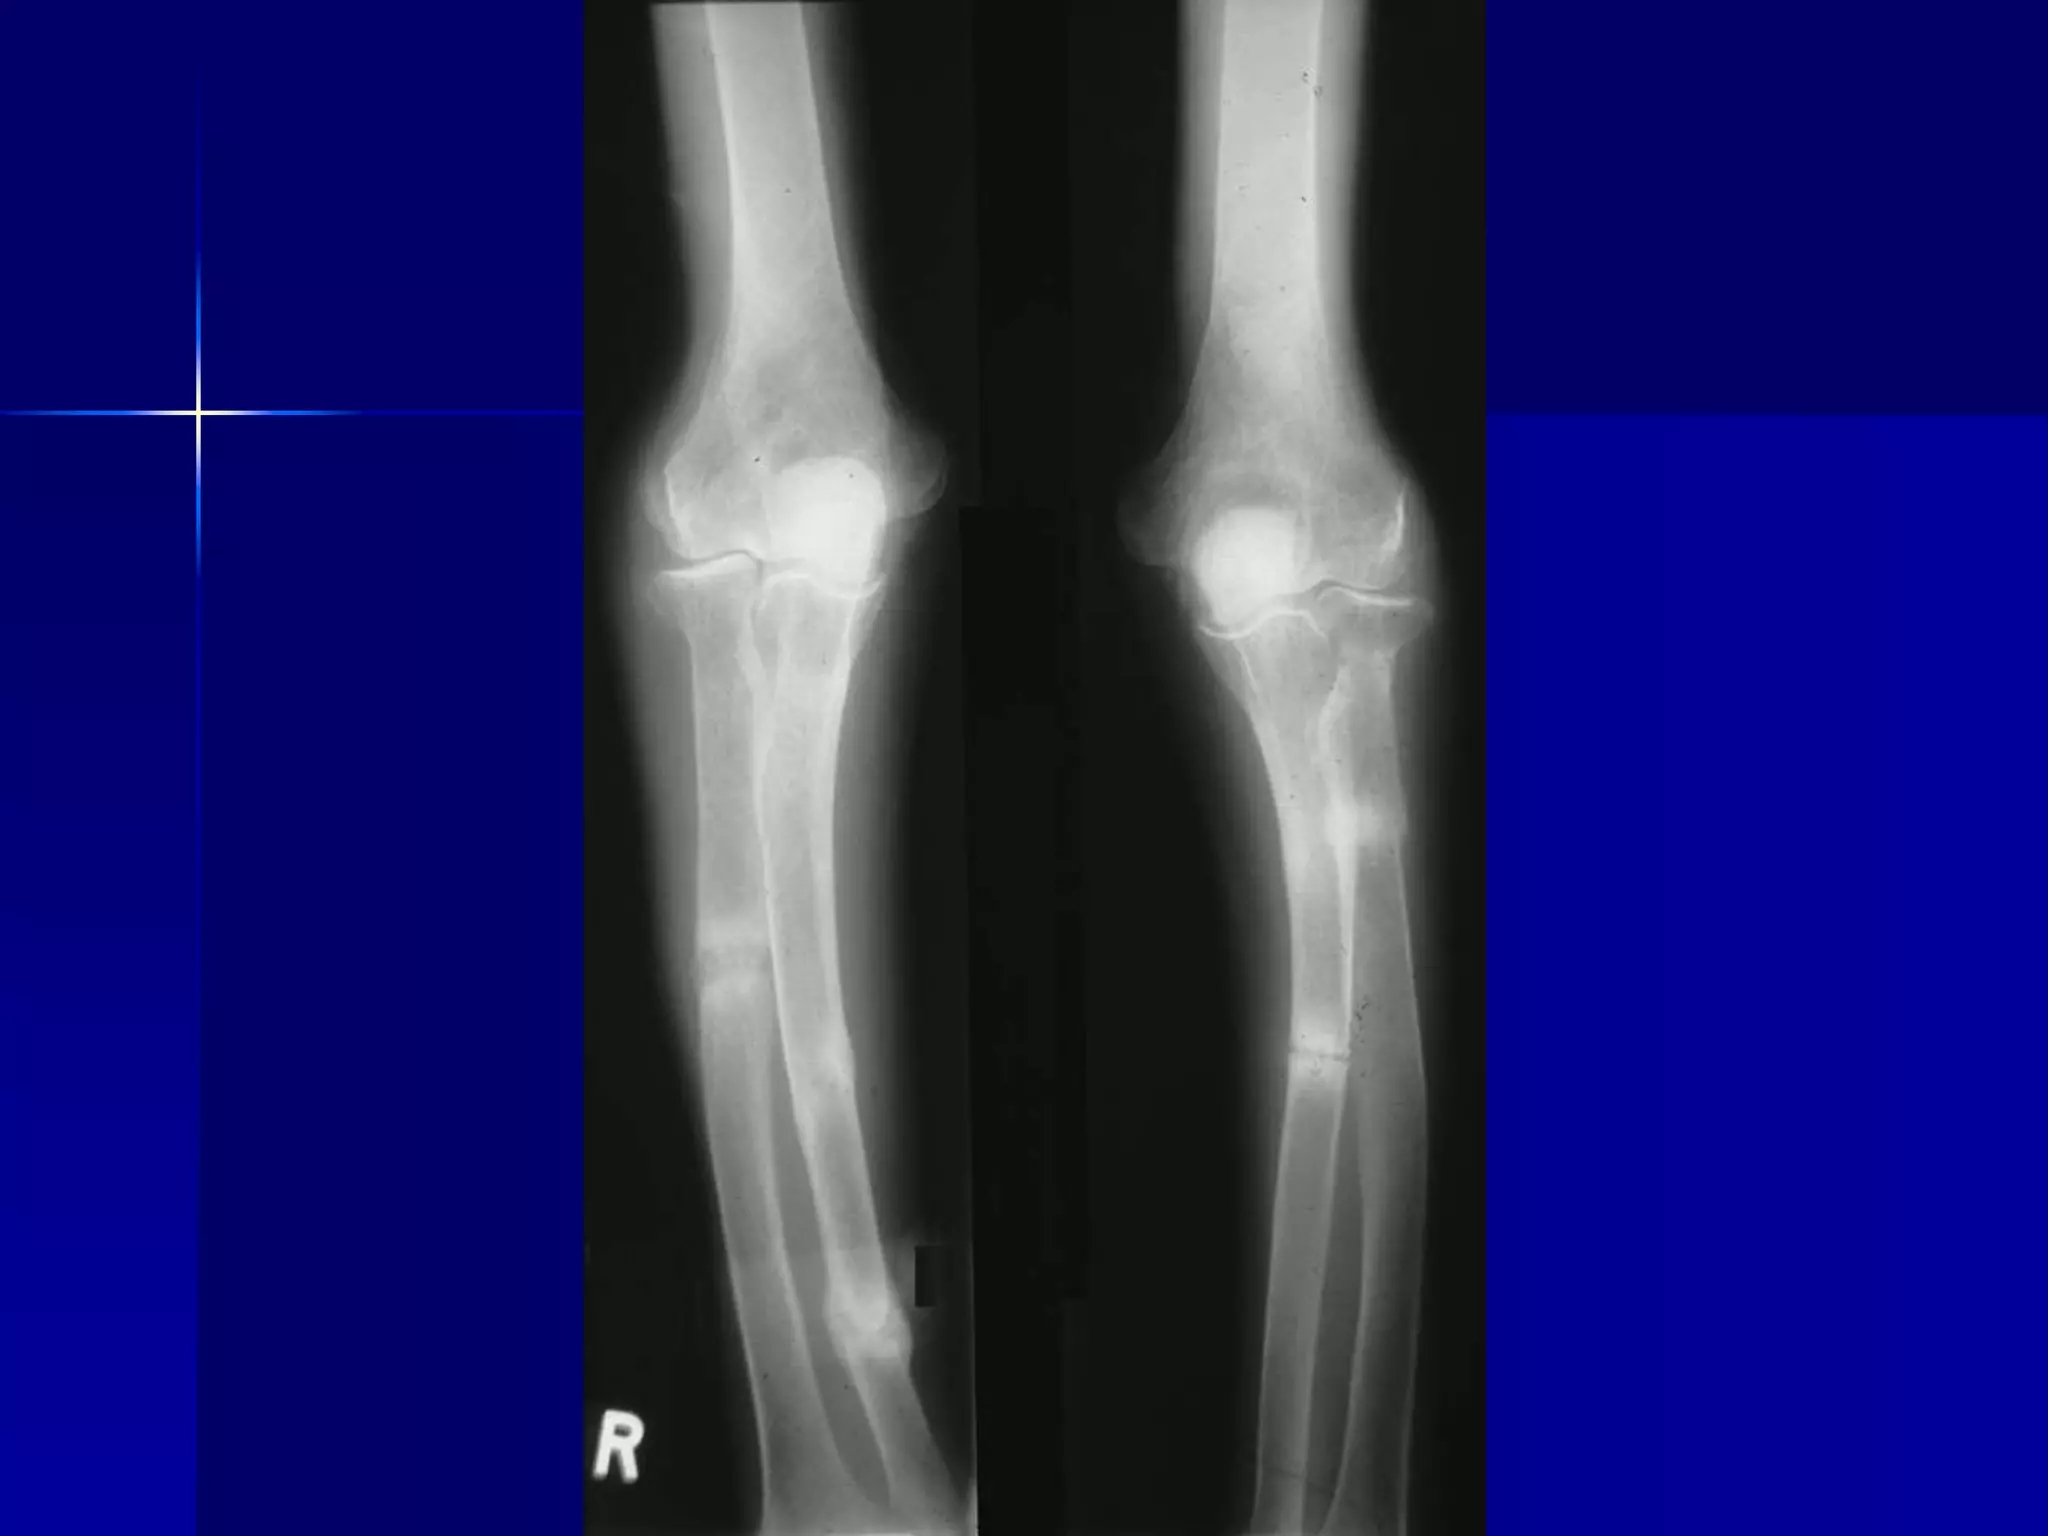

Case

 This 19 year old male presented with a

history of 3 stone weight loss (42 lbs to

our US cousins, 19kg to the metric world)

over a period of three months. He

complained of malaise and was anaemic.

Endoscopy of the upper gastrointestinal

tract was normal.

 A barium small bowel meal was

performed.